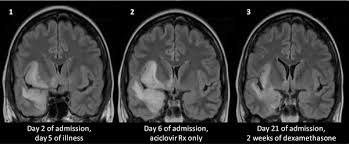

Neuroimaging Of Herpesvirus Infections In Children Springerlink

Neuroimaging Of Herpesvirus Infections In Children Springerlink from media.springernature.com

It is reasonable to obtain an mri when patients are asymptomatic to ensure that no other abnormality is present which may be causing a recurrent chemical meningitis (e.g. Multilocularis.the larval stage is the cause of hydatid disease in humans 1. The changes spare the basal ganglia, a feature which is helpful in distinguishing an mca infarct with hemorrhagic transformation from herpes simplex encephalitis, the diagnosis in this case. The differential diagnoses include limbic encephalitis (paraneoplastic), gliomatosis cerebri, and status epilepticus. It is estimated to occur in ~2% of pati. 10 public playlist includes this case Spinal hydatid disease is an uncommon manifestation of hydatid disease, caused by the larval stage of echinococcus granulosus, or less commonly e. This patient went on to have hsv encephalitis proven on csf pcr.

Herpes simplex encephalitis typically manifests in older adults (about 50% of cases) with headache, fever, altered sensorium, and even seizure.

Mri demonstrates extensive edema in the right temporal lobe with areas of intrinsic high t1 signal, in keeping with hemorrhage. Become a gold supporter and see no ads. For a general discussion, and for links to other system specific manifestations, please refer to the article on coccidioidomycosis. This patient went on to have hsv encephalitis proven on csf pcr. This patient went on to have hsv encephalitis proven on csf pcr. Spinal hydatid disease is an uncommon manifestation of hydatid disease, caused by the larval stage of echinococcus granulosus, or less commonly e. Given the history of fever and seizures coupled with the mri findings of bilateral mesial temporal lobe changes, herpes encephalitis requires clinical consideration. Multilocularis, and describes a spectrum of disease involving the spinal cord, the spine, or both. Herpes simplex encephalitis radiology case radiopaedia mri demonstrates extensive edema in the right temporal lobe with areas of intrinsic high t1 signal, in keeping with hemorrhage. Hsv encephalitis | radiology case | radiopaedia.org. Two subtypes are recognised which differ in demographics, virus, and pattern of involvement. It is estimated to occur in ~2% of pati. Reference osborn a, et al.

Two subtypes are recognised which differ in demographics, virus, and pattern of involvement. Mri is the diagnostic modality of choice abnormal in 90%; A brain biopsy was performed and the histology was consistent with encephalitis. Reference osborn a, et al. Radiopaedia is free thanks to our supporters and advertisers.